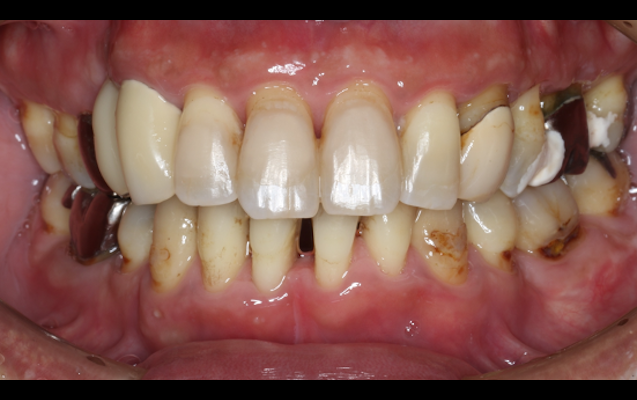

歯を長持ちさせるために必要なことは「歯の外に対しての歯周病治療、歯の中に対しての根管治療」です。両者が複雑に絡んでいるケースもあり、それぞれに対処が必要な場合もあります。そのような場合でも歯科用CT・マイクロスコープを活用することで対応することが可能です。

昨今では重度歯周病に対する治療の研究が進み、現在では歯周病により溶けた歯槽骨の再生が可能となっています。根の先端を超えるような骨吸収が起きていたとしても残すことができるとの報告もあります。

当院には、保存不可と診断された歯を保存してきた多数の実績があります。

難易度の高い治療ではありますが、歯科用CTによる正確な診断、マイクロスコープを用いた精密な治療により可能となります。